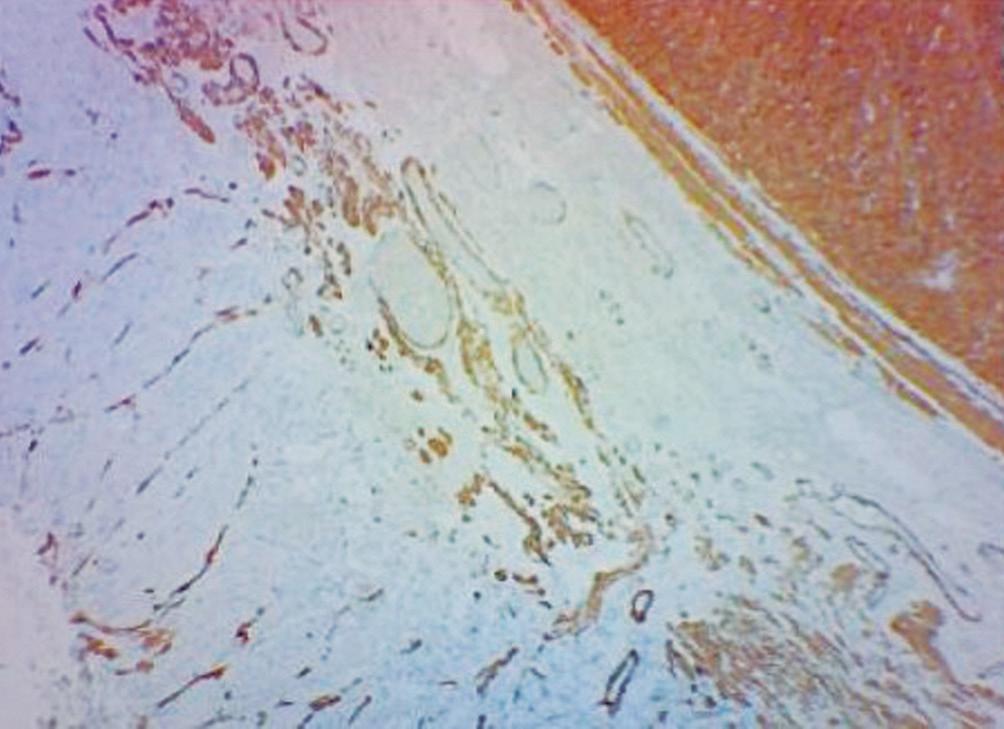

Evaluación de un paciente con dolor epigástrico y hallazgos sincrónicos infrecuentes

Roy López Grove, Daniela Soloaga, Juan Carlos Spina

Roy López Grove, Daniela Soloaga, Juan Carlos Spina 398